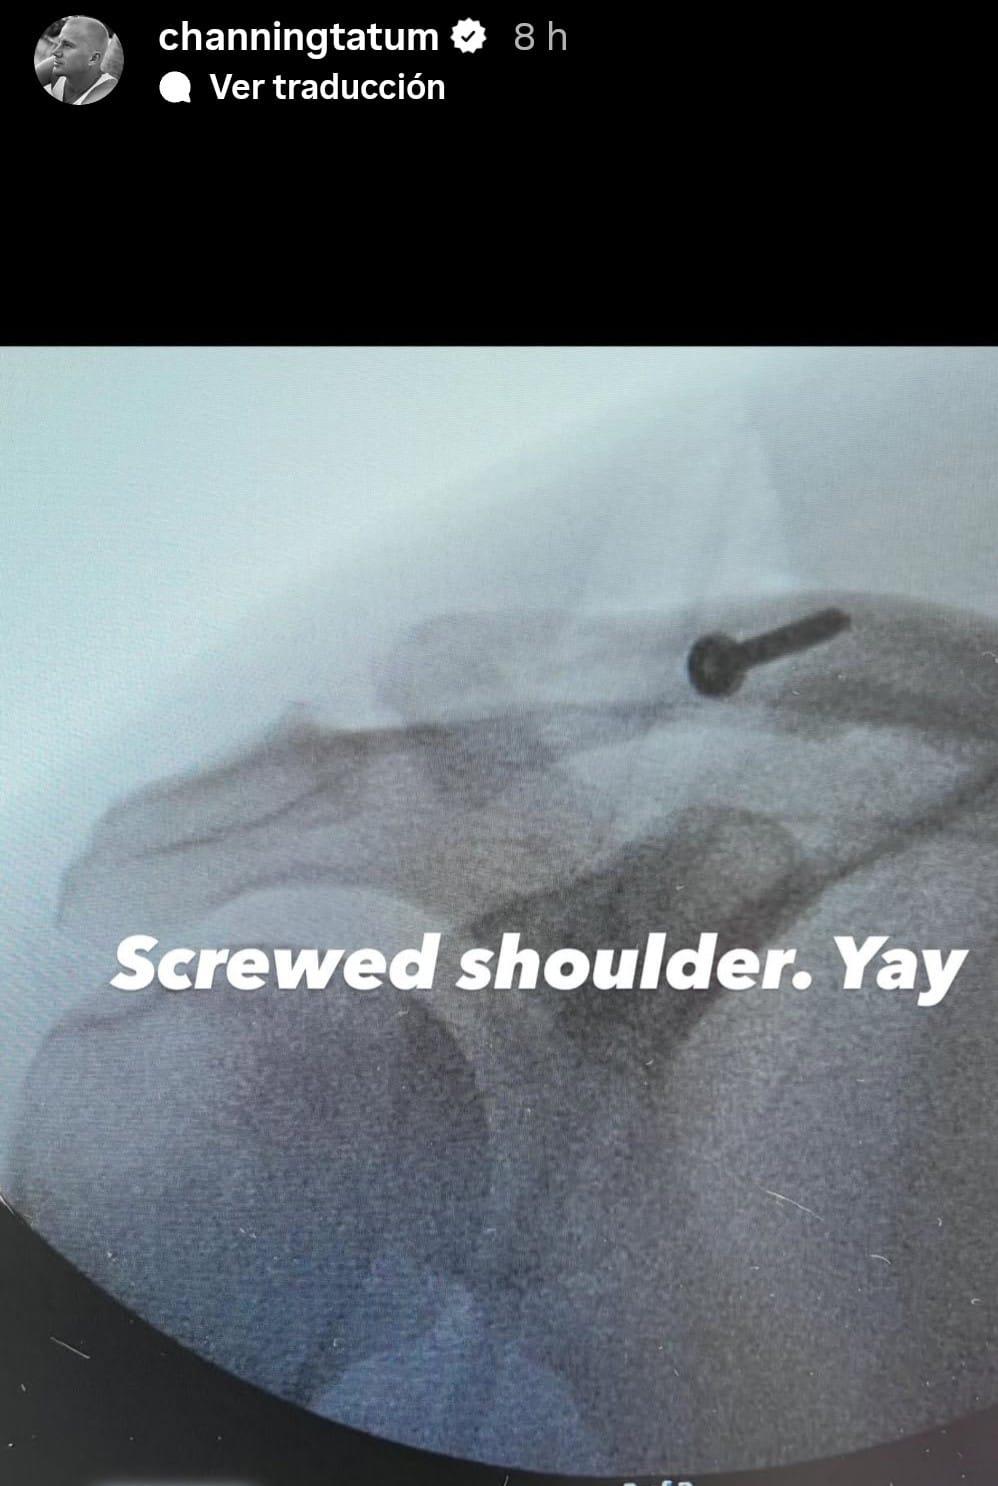

En una segunda fotografía, ya posoperatoria, mostró la misma zona tras la intervención quirúrgica. “Hombro atornillado. ¡Genial!”, escribió, acompañado de la radiografía en la que se observa un tornillo de gran tamaño que mantiene unidos los huesos.

Radiografía del hombro de Channing Tatum después de la cirugía, se aprecia el tornillo que le tuvieron que colocar.